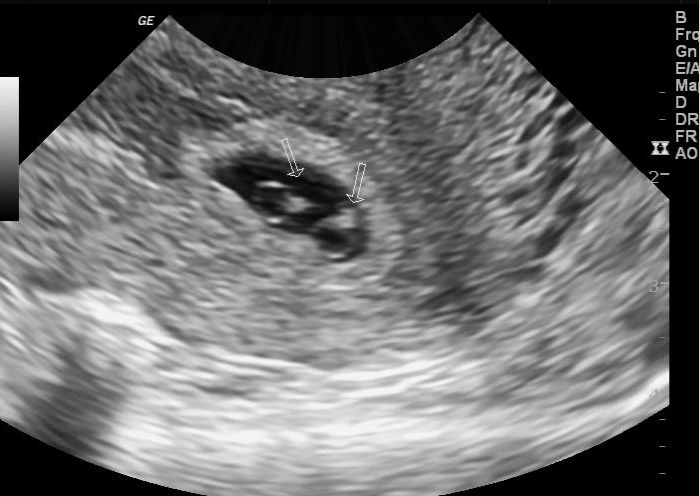

Na imagem abaixo os achados são compatíveis com uma gestação gemelar monocoriônica e diamniótica (MoDi):

- Uma placenta (monocoriônica)

- Dois sacos amnióticos (diamniótica)

- Membrana divisória fina entre os embriões.